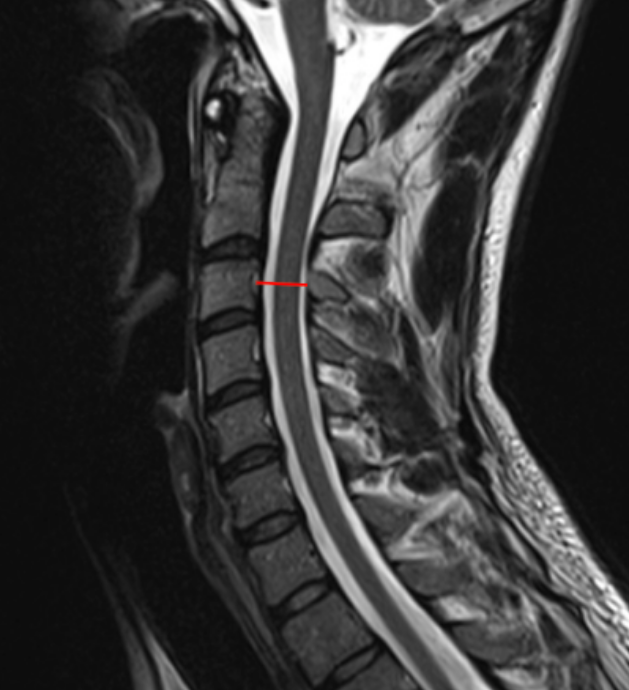

Sagittal canal diameter is a direct linear measurement of the anteroposterior (AP) dimension of the cervical spinal canal, reflecting the space available for the spinal cord. On MRI, this measurement incorporates both osseous and soft-tissue boundaries, making it the most accurate imaging modality for evaluating true canal compromise.

Reduced sagittal canal diameter correlates strongly with cervical spinal stenosis, myelopathy, and increased risk of neurologic injury, particularly in the presence of degenerative disc disease, posterior osteophytes, ligamentum flavum hypertrophy, or disc herniation.

•  Select a mid-sagittal T2-weighted MRI slice that clearly visualizes:

• Identify the vertebral level of interest (commonly C3–C7).

• At the selected level:

• Identify the posterior margin of the vertebral body or disc–osteophyte complex (anterior canal boundary).

• Identify the anterior margin of the ligamentum flavum or lamina (posterior canal boundary).

• Using digital calipers, measure the shortest anteroposterior distance (mm) between these two structures.

• Repeat measurements at multiple levels if needed and record the smallest diameter, as this represents the most clinically relevant stenotic level.